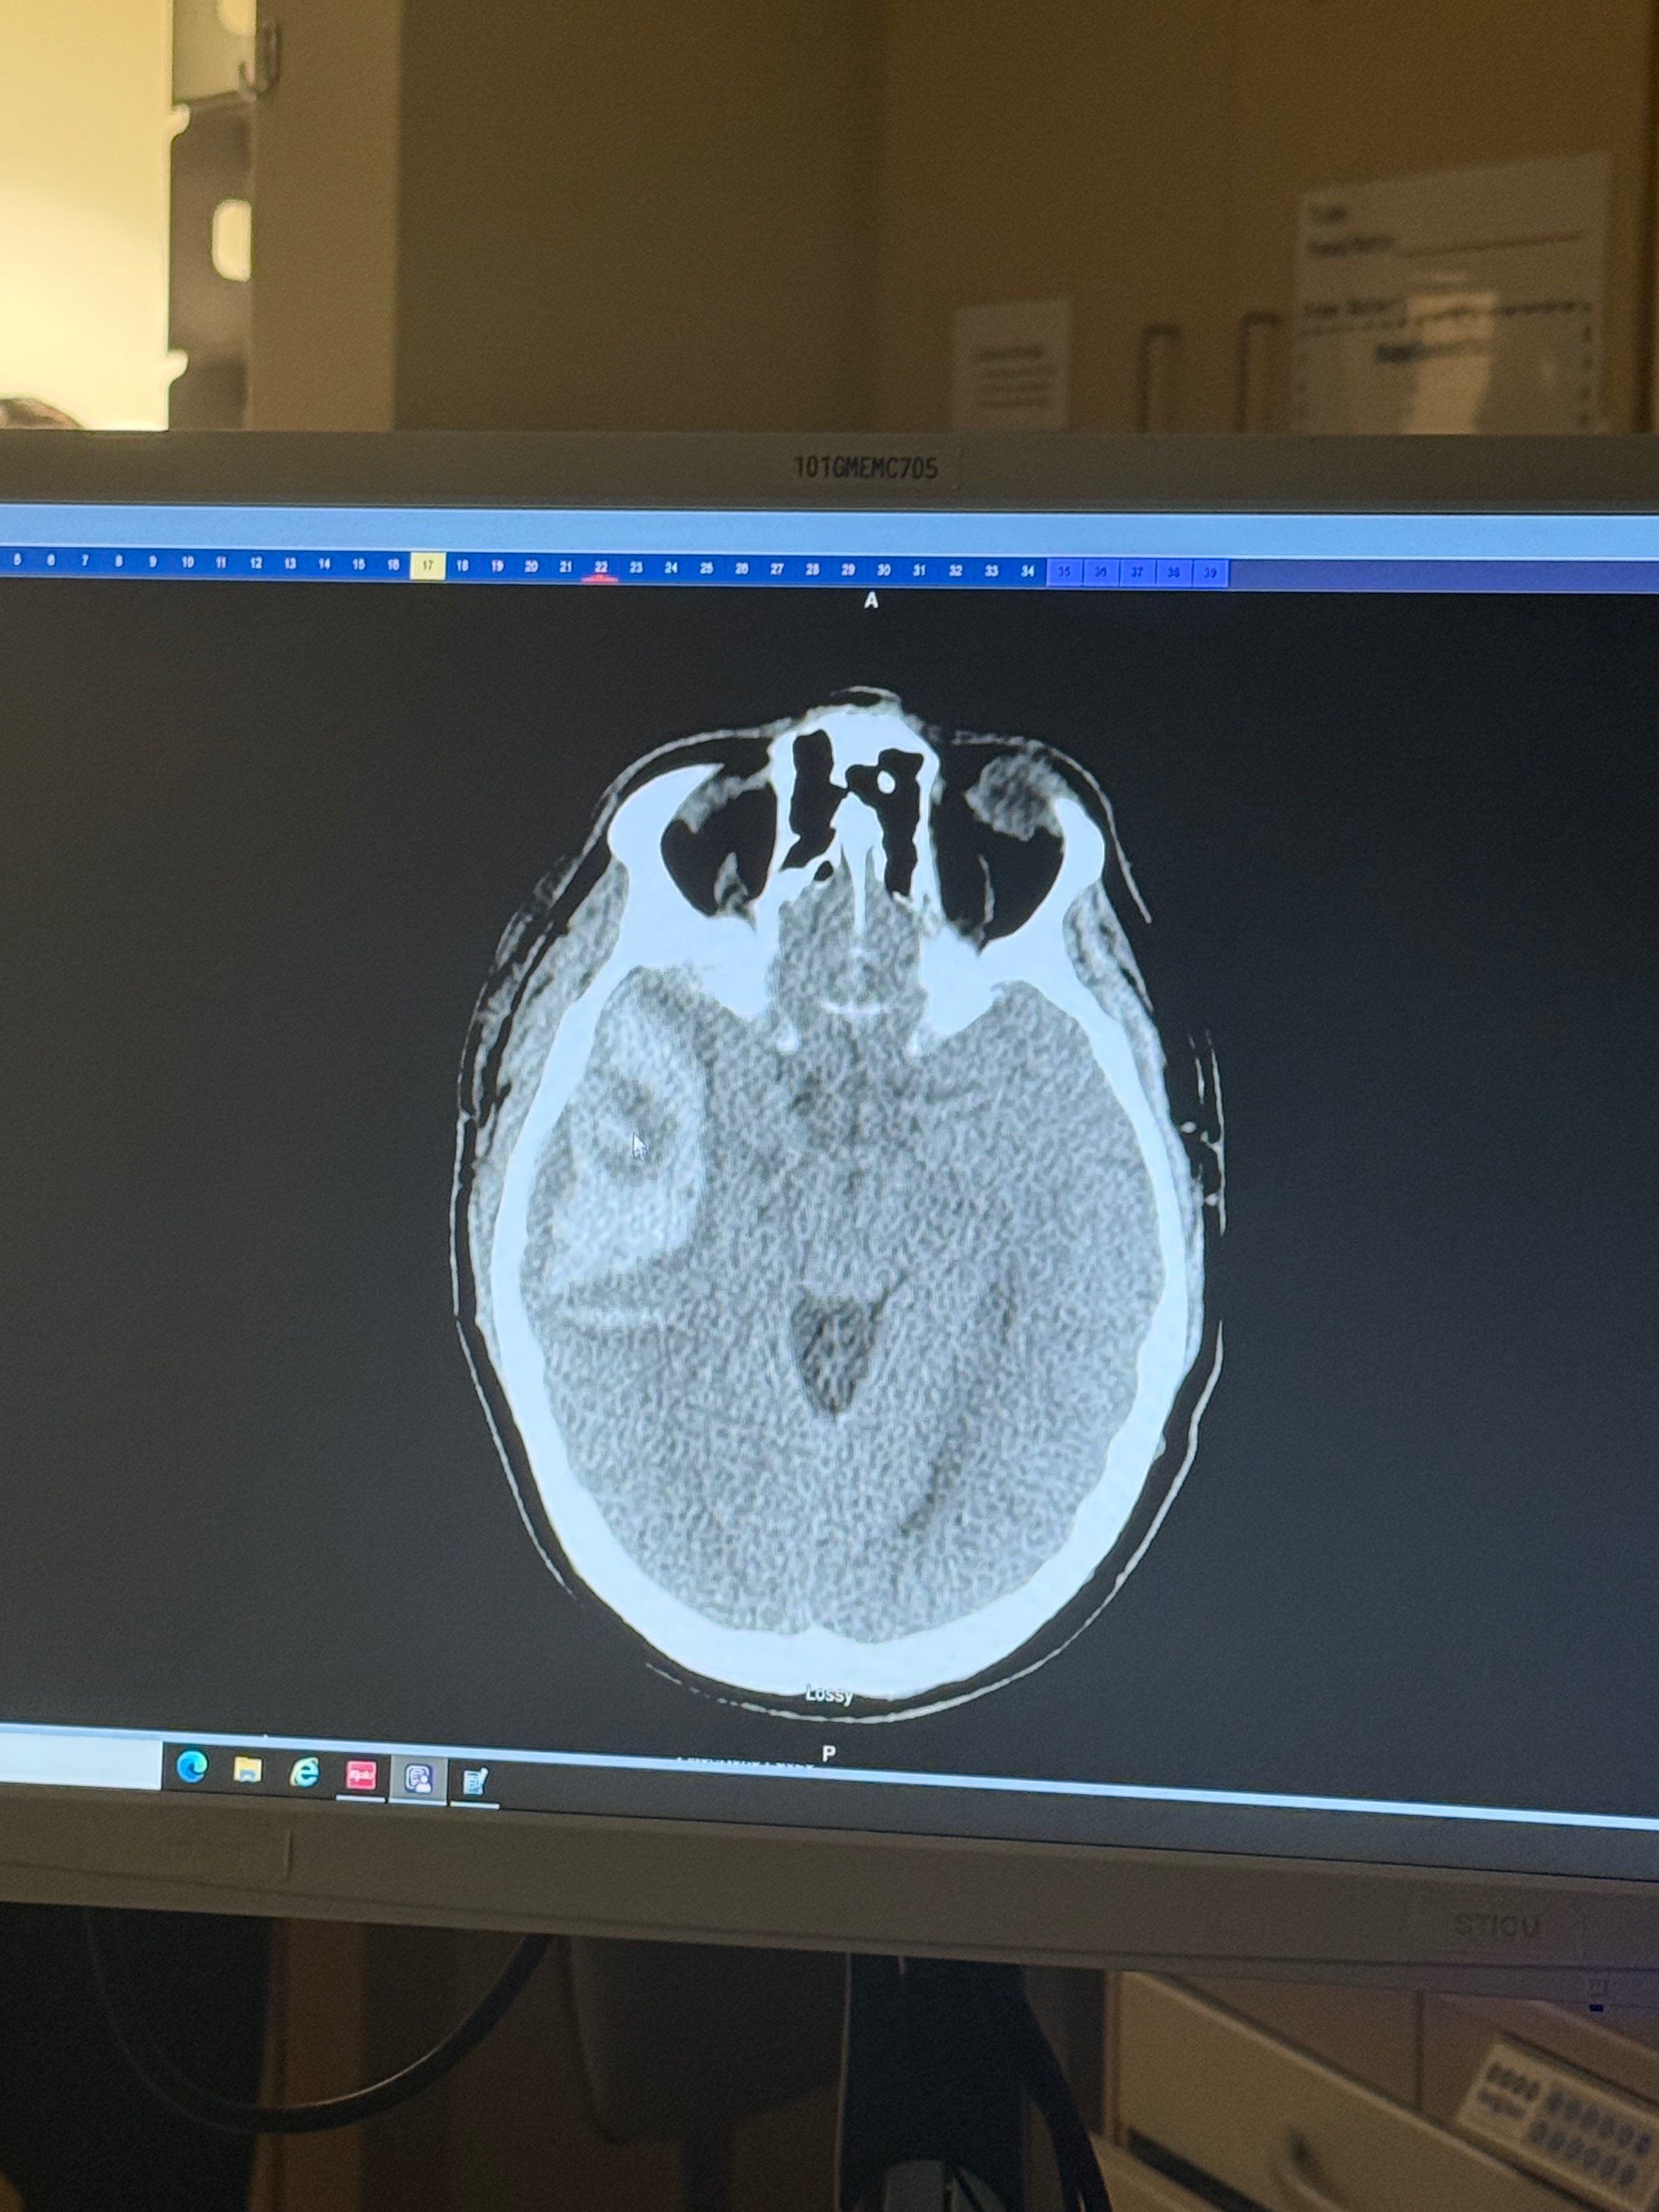

My daddy, Bruce Waldon, and sister Gracee waldon were attacked by several men and woman while camping, which resulted in a severe brain bleed and 40 stitches on his neck. My dad is still in critical condition but is stable by the grace of God.